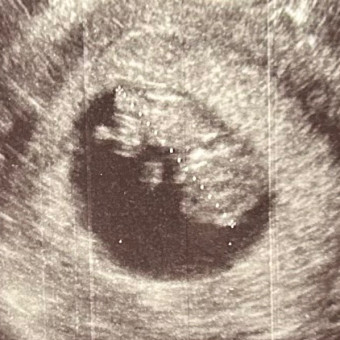

Hello friends and family! This is Brianna and Justin’s registry for peanut!! Theodore Abel Weaver is HERE!! He has made an early arrival on March 12, 2026 at 10:38pm. 🖤